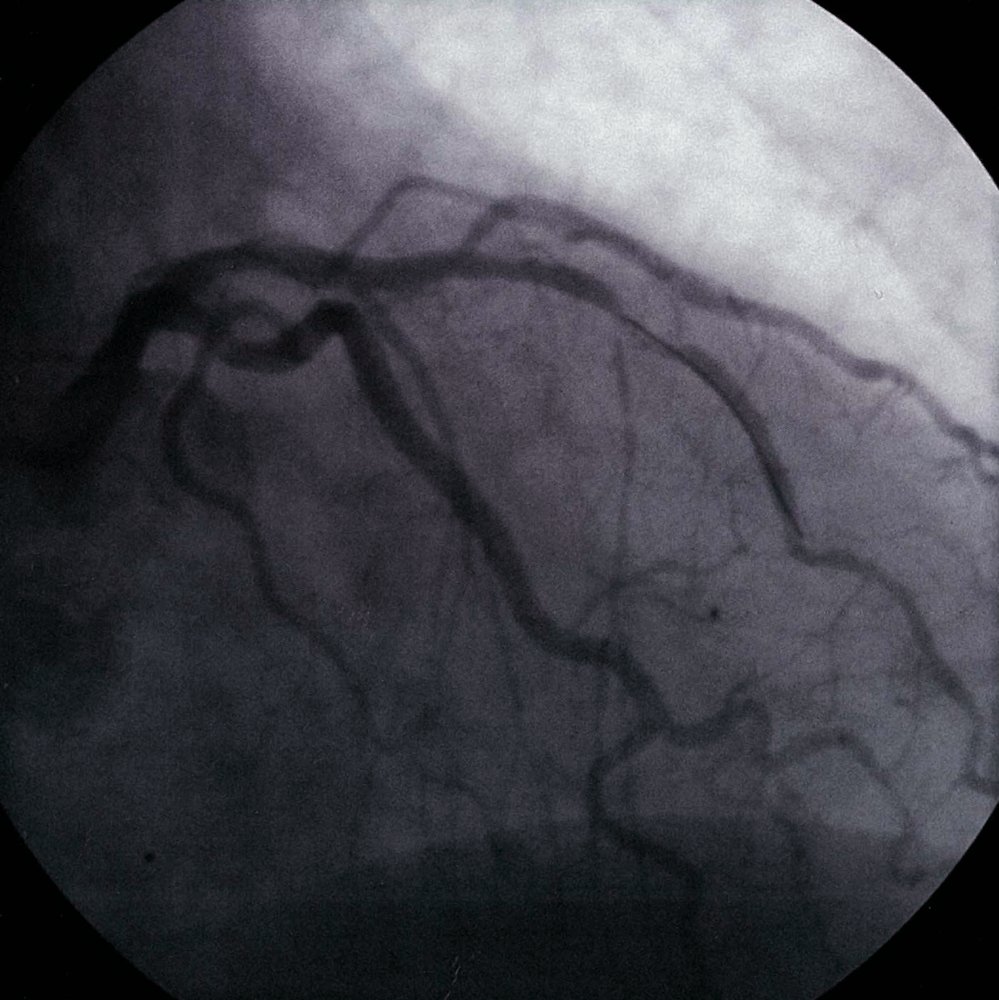

коронарография қай уақытқа дейін жасалуы тиіс?

![]()

оптимальды ИМ басталғаннан 90мин ішінде

120мин ішінде